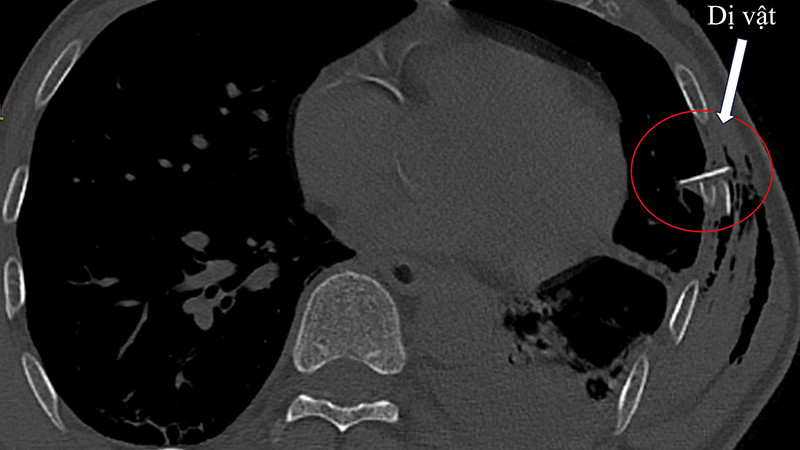

Sau đó, bệnh nhân có cơn đau ngực tăng dần, đau nhiều đến nỗi không dám thở, có tình trạng suy hô hấp, hình ảnh XQ phổi chưa ghi nhận bất thường khác ngoài gãy các xương sườn VI, VII, VII. Bệnh nhân được chụp cắt lớp ngực và ghi nhận tràn khí, tràn máu màng phổi với một hình ảnh mảnh xương sườn đâm vào nhu mô phổi. Bệnh nhân được hội chẩn để phẫu thuật cấp cứu.

| Bệnh nhân được phẫu thuật nội soi khoang màng phổi hoàn toàn, mảnh xương sườn gãy vụn được lấy ra. |

Sau hơn một giờ phẫu thuật nội soi khoang màng phổi hoàn toàn, mảnh xương sườn gãy vụn đã được lấy ra, vết thủng ở nhu mô phổi đã được khâu kín, máu được cầm và khoang màng phổi được làm sạch.